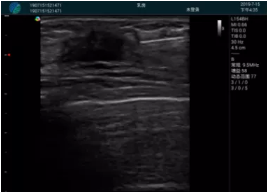

腺體內(nèi)部清晰顯示一低回聲塊影,形態(tài)不規(guī)則,邊界模糊,邊緣呈毛刺狀,內(nèi)部見砂礫樣鈣化

M20引導(dǎo)下穿刺活檢術(shù)

M20查看:囊內(nèi)回聲均勻,邊界清晰,囊壁光滑

M20引導(dǎo)抽吸術(shù)后囊腫消失,原區(qū)域空腔形成,脂肪層與腺體層架構(gòu)發(fā)生改變